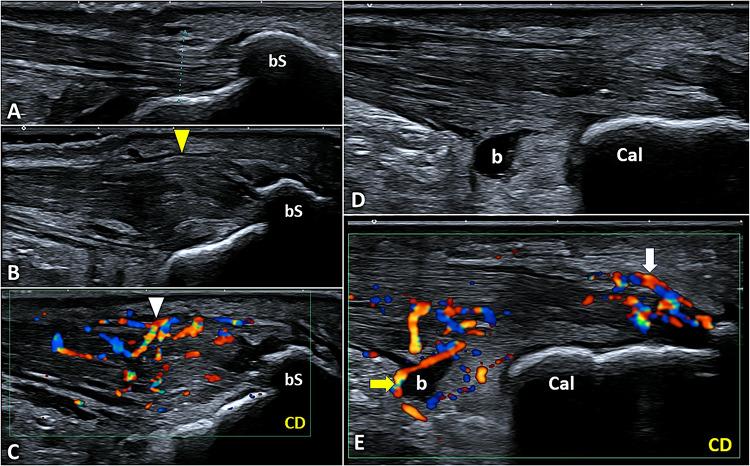

Padel is a racket sport, combining high-frequency and low-intensity athletic gestures, that has been gaining growing scientific interest in recent years. Musculoskeletal injuries are very common among padel players with an incidence rate of 3 per 1000 h of training and 8 per 1000 matches. To the best of our knowledge, a comprehensive collection describing the most common sonographic findings in padel players with musculoskeletal injuries is lacking in the pertinent literature. In this sense, starting from the biomechanical features of padel-specific gestures we have reported the ultrasonographic patterns of most frequent injuries involving the upper limb, the trunk, and the lower limb. Indeed, comprehensive knowledge of the biomechanical and clinical features of musculoskeletal injuries in padel is paramount to accurately perform a detailed ultrasound examination of the affected anatomical site. So, the present investigation aims to provide a practical guide, simple and ready-to-use in daily practice, to optimize the sonographic assessment of padel players by combining it with the clinical findings and the biomechanical features of athletic gestures.